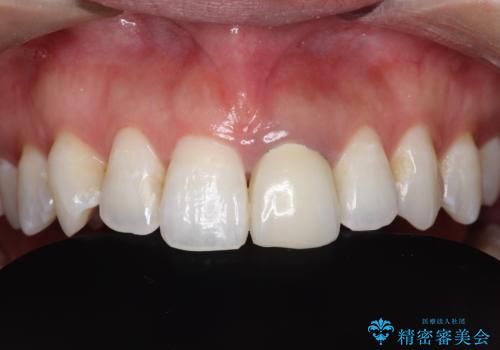

- 右上奥歯の歯肉から出血があり異和感をおぼえ来院された患者様です。

歯周治療と補綴治療を行いました。

以前の被せ物を除去し、仮歯に変えてすぐに異和感がとれました。

歯周治療を行い、歯肉が引き締まってから補綴治療しました。